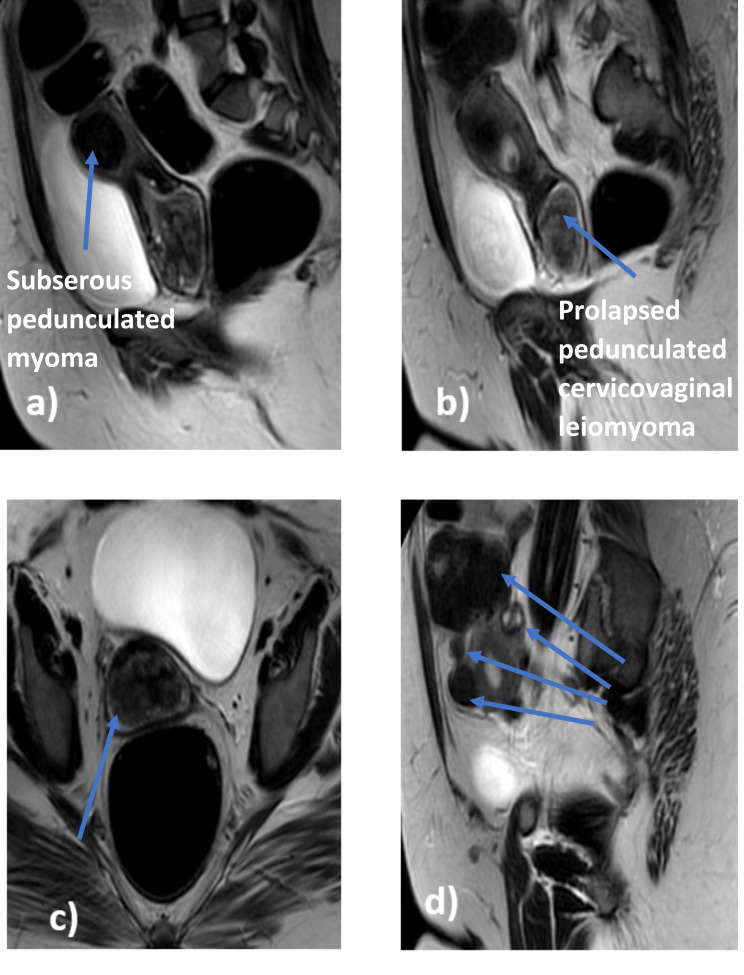

平滑肌瘤是女性生殖道最常见的良性肿瘤。它可以发生在粘膜下、壁内或粘膜下。粘膜下亚型占全部病例的5%,可出现带蒂或脱垂于子宫腔外,引起阴道出血和盆腔疼痛,显著影响生活质量,尤其是较大的平滑肌瘤。这种情况的处理可能需要阴道通道,这可能会破坏处女膜的完整性,在保守的社区是不被接受的。在这里,我们提出了一种创新的保留处女膜的腹腔镜-耻骨上宫腔镜入路(LASHA),通过阴道前切开术和子宫肌瘤切除术,用于子宫内膜腔探查和治疗一位处女患者脱垂的有蒂宫颈阴道平滑肌瘤。一位30岁的处女因过去6个月大量月经出血就诊。腹部超声示子宫肿大伴多发子宫肌瘤;最大的一个位于宫颈阴道区,充满阴道,呈实性低回声肿块,轮廓清晰,充满阴道边缘,提示脱垂,有带蒂的宫颈阴道平滑肌瘤(5.7x6.6x 8.3 cm)。其他浆膜下和壁内肌瘤的范围为2至7厘米。根据患者的意愿,决定采用LASHA方法来保持处女膜的完整性,从而成功切除肿瘤。总之,LASHA入路治疗脱垂、带蒂宫颈阴道平滑肌瘤在保守社会中是一种充分、安全且被社会接受的替代方法。因此,在拒绝阴道入路的处女中,腹腔镜的适应症可以扩展到子宫内膜腔探查和治疗宫颈阴道平滑肌瘤。然而,这项技术需要足够的设备和技能在腹腔镜手术。

Leiomyoma is the most common benign tumor of the female genital tract. It may develop subserous, intramural, or submucous. The submucous subtype accounts for 5% of all cases, and it may become pedunculated or prolapse outside the uterine cavity, resulting in vaginal bleeding and pelvic pain, significantly impacting the quality of life, especially for larger leiomyomas. The management of such cases may require vaginal access, which may disrupt hymen integrity and is not accepted in conservative communities. Here, we present an innovative hymen-conserving Laparoscopic-And-Suprapubic Hysteroscopic Approach (LASHA) via anterior colpotomy and myomectomy for endometrial cavity exploration and management of a prolapsed pedunculated cervicovaginal leiomyoma in a virgin patient. A 30-year-old virgin presented to the clinic with heavy menstrual bleeding for the past 6 months. Abdominal ultrasound showed an enlarged uterus with multiple uterine myomas; the largest one was in the cervicovaginal zone, filling the vagina, showing a solid hypo-echoic mass, well delineated, filling the vaginal margins, and suggesting a prolapsed, pedunculated cervicovaginal leiomyoma (5.7x6.6x 8.3 cm). Other subserosal and intramural myomas ranged from 2 to 7 cm. The LASHA approach was decided to preserve the hymen's integrity based on the patient's desire, resulting in a successful tumor excision. In summary, the LASHA approach of a prolapsed, pedunculated cervicovaginal leiomyoma is an adequate, safe, and socially accepted alternative in conservative societies. Therefore, the indications of laparoscopy could be extended to endometrial cavity exploration and managing cervicovaginal leiomyoma in virgin women rejecting vaginal approaches. However, this technique necessitates adequate equipment and skills in laparoscopic surgery.